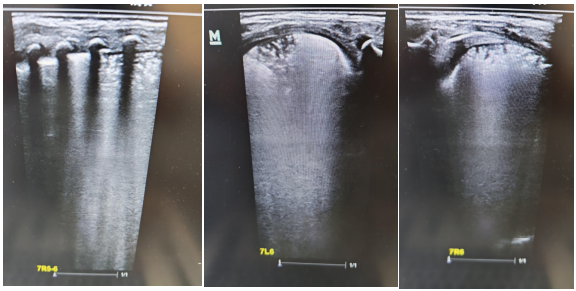

術前肺部超聲及CT均提示雙肺實變明顯